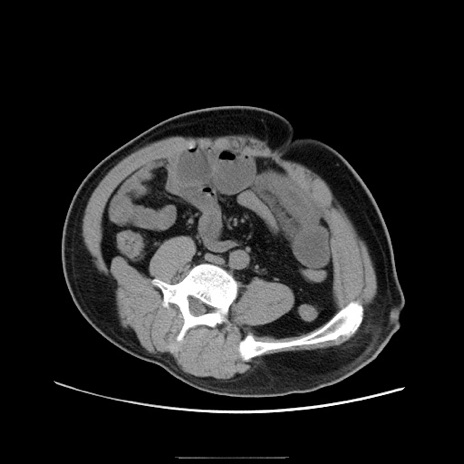

症例22(横断像)

【症例】50歳代男性

【主訴】腹痛

【現病歴】AVMからの被殻出血のため回復期リハ病棟入院中。 本日午後3時頃急に下腹部痛が出現した。

【既往歴】AVM、被殻出血、虫垂炎、高血圧

【身体所見】意識晴明、左半身不全麻痺、会話の理解は良好、36.5°C、腹部:膨隆、全体に板状硬、下腹部正中に圧痛点あり、反跳痛-、筋性防御不明、右下腹部にope scar

【データ】WBC 9400、CRP 0.06